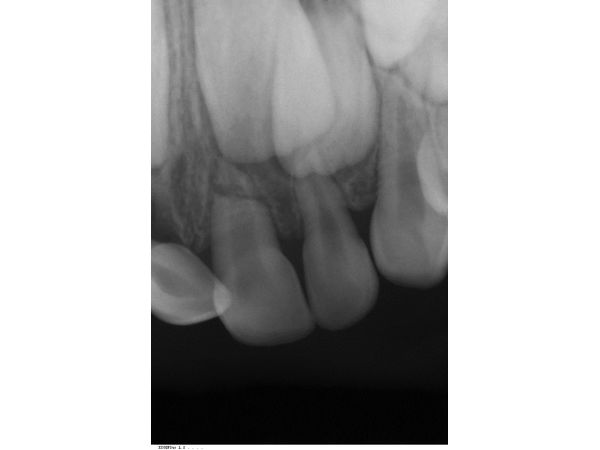

По результатам прицельной рентгенограммы, в лунках правых верхних резцов корней не было. Она также показала перелом в верхушечной трети корня левого центрального резца.

Перелом корня зуба 61, полный вывих (экзартикуляция) зубов 51 и 52.